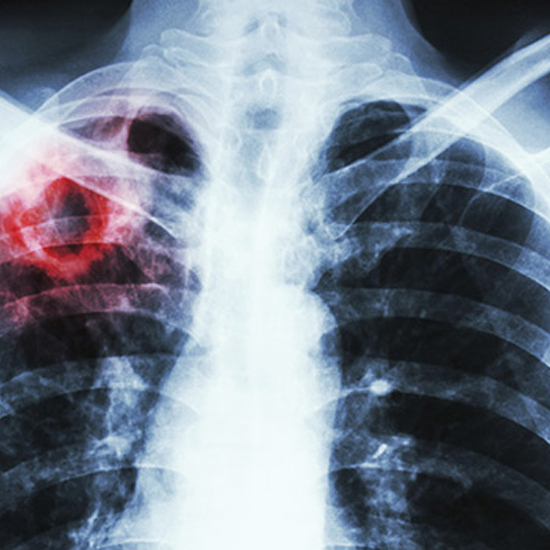

Пандемія коронавірусу, що накладається на високі рівні поширення туберкульозу, може мати тяжкі наслідки. Про це свідчить досвід Китаю, який успішно протидіє епідемії COVID-19. Водночас у цій країні виникли проблеми з діагностикою туберкульозу та забезпеченням лікування цієї хвороби. Під час пандемії коронавірусу хворі на туберкульоз входять до групи ризику. У них вже наявне ураження легеневих тканин. Для цих пацієнтів найголовніше — самоізоляція вдома.